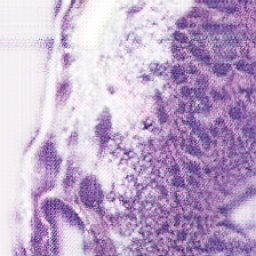

For Target Domain, the MHIST dataset [2] is used (available at https://bmirds.github.io/MHIST/ ), which contains high quality H&E stained histopathology images suitable for learning realistic color and texture distributions.Jana The dataset contains 3,152 H&E images. Some examples are displayed in Figure 1.